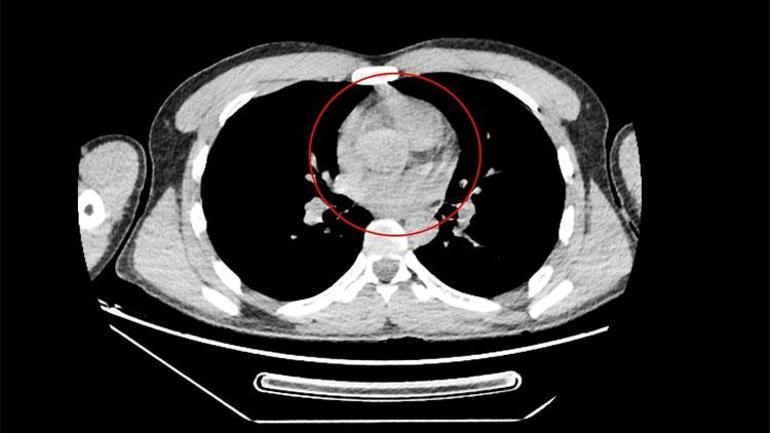

Van’dan İstanbul’a giden bir yolcu otobüsünde seyahat eden yabancı uyruklu Zadeh Ahmed Narziveh, araç Ankara şehirlerarası otobüs terminali AŞTİ’ye vardığında fenelaştı. Durumunun bildirilmesi üzerine gelen 112 Acil Servis ekiplerince ilk müdahalesi yapılan Narziveh, ardından ambulans ile şehir hastanesine kaldırıldı. Narziveh’in, hastanede çekilen röntgeninde midesinde uyuşturucu kapsülleri görülünce Narkotik polis ekiplerine bilgi verildi. Hastaneye gelen Narkotim ekiplerinin gözetiminde ameliyata alınan Narziveh’in midesinde 2’si patlamış, 72 kapsül halinde 890 gram uyuşturucu madde metamfetamin çıkarıldı.